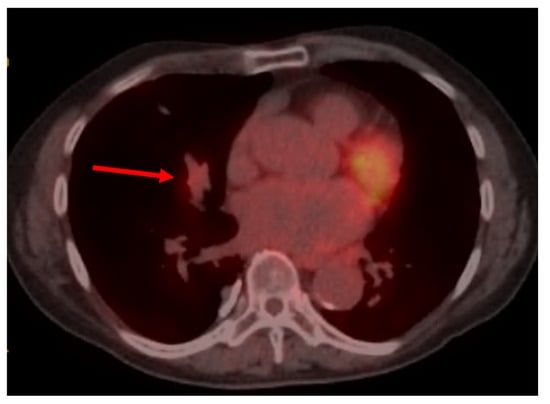

Not All PET-Avid Endobronchial Lesions Are Malignant: A Case of Chronic Foreign Body Aspiration

Background: Low-dose CT scanning is a key tool in lung cancer screening, enabling the detection of clinically significant abnormalities in asymptomatic individuals and often prompting further diagnostic evaluation. Case Presentation: We describe the case of an 80-year-old man with a heavy smoking history [...] Read more.

Background: Low-dose CT scanning is a key tool in lung cancer screening, enabling the detection of clinically significant abnormalities in asymptomatic individuals and often prompting further diagnostic evaluation. Case Presentation: We describe the case of an 80-year-old man with a heavy smoking history who was found to have a new right middle lobe collapse on screening CT. Subsequent positron emission tomography-computed tomography (PET/CT) imaging demonstrated mild fluorodeoxyglucose (FDG) uptake (SUVmax 2.7), raising concern for a low-grade endobronchial malignancy versus mucoid impaction. Flexible fiberoptic bronchoscopy revealed a large exophytic endobronchial mass occluding the airway. Histopathologic examination of the biopsy sample unexpectedly revealed vegetable material, consistent with chronic foreign-body aspiration. Discussion: Unrecognized aspiration events are relatively common in elderly adults and can mimic malignancy on imaging. This case highlights an important diagnostic pitfall: inflammatory endobronchial processes, including foreign-body granulomas, can demonstrate FDG uptake and mimic malignancy. Conclusion: Clinicians should maintain a broad differential diagnosis when evaluating PET-avid endobronchial lesions, especially in elderly patients. Full article

Show Figures

Figure 1